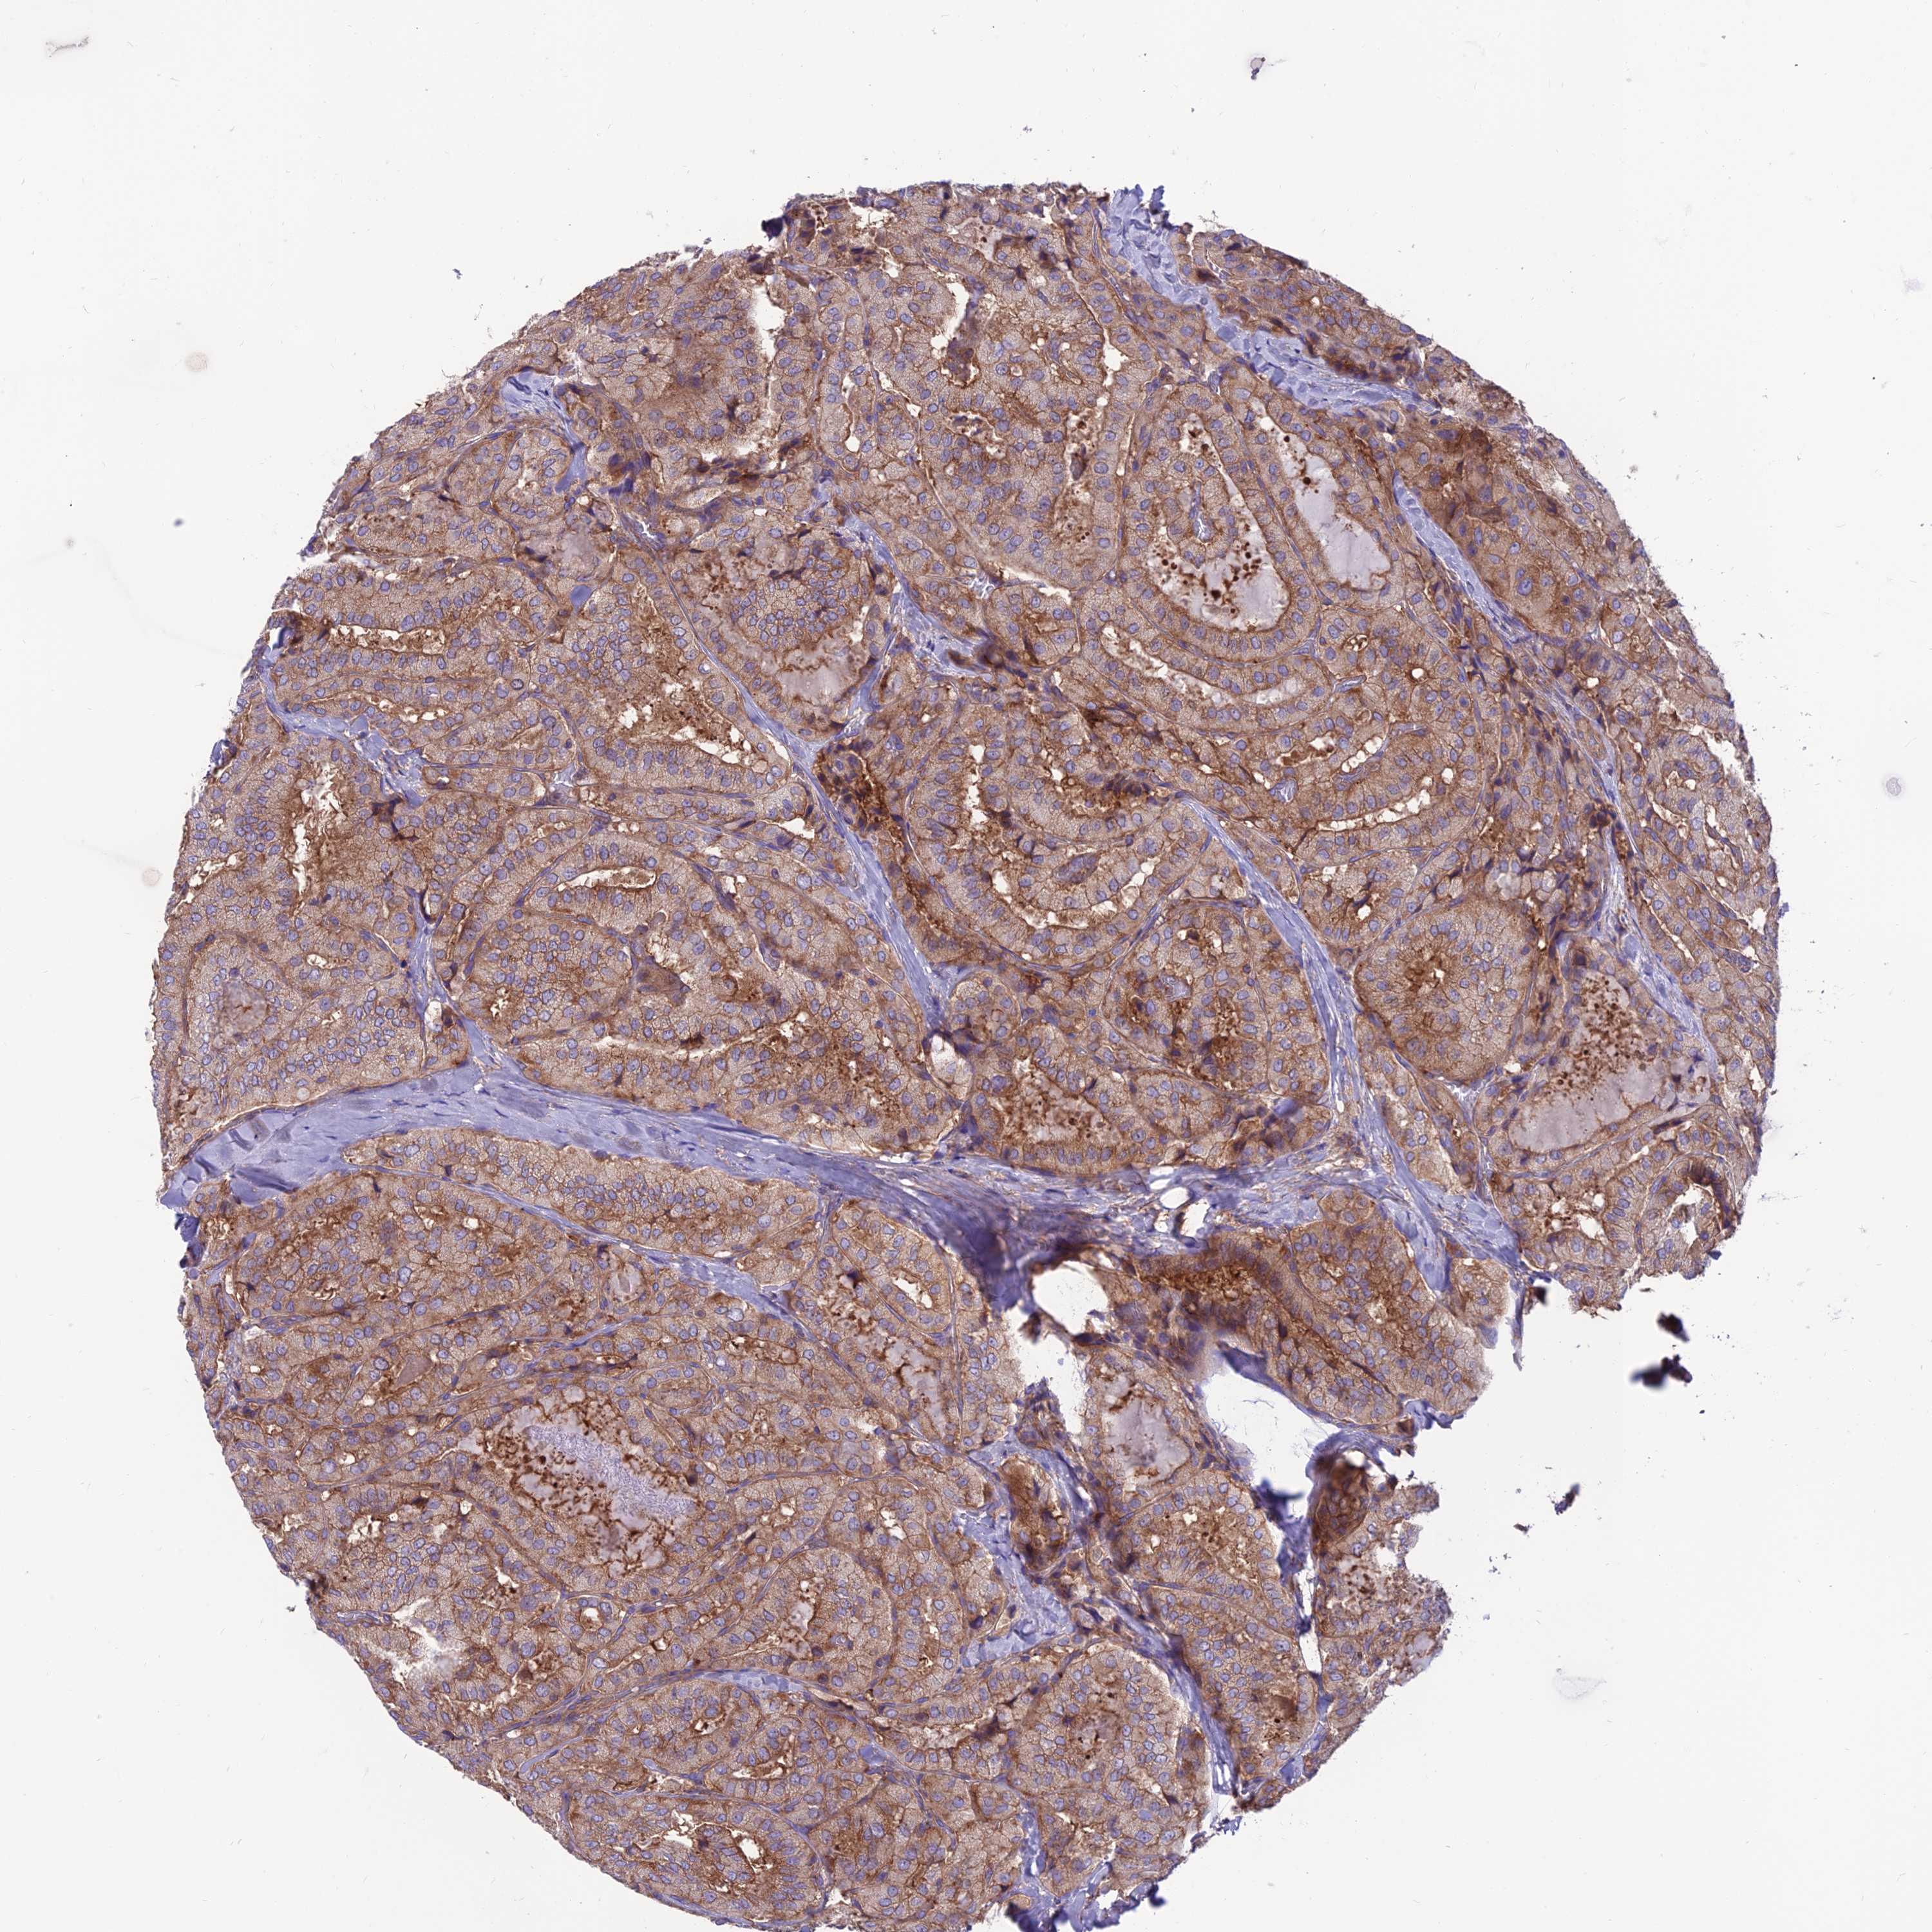

THYROID CANCER - Protein expressioni

A mouse-over function shows sample information and annotation data. Click on an image to view it in a full screen mode. Samples can be filtered based on level of antibody staining by selecting one or several of the following categories: high, medium, low and not detected. The assay and annotation is described here.

Note that samples used for immunohistochemistry by the Human Protein Atlas do not correspond to samples in the TCGA dataset.

Antibody stainingi

Antibody staining in the annotated cell types in the current human tissue is reported as not detected, low, medium, or high, based on conventional immunohistochemistry profiling in selected tissues. This score is based on the combination of the staining intensity and fraction of stained cells.

Each image is clickable and will lead to virtual microscopy that enables deeper exploration of all samples and also displays staining intensity scores, fraction scores and subcellular localization as well as patient and tissue information for each sample.

Antibody HPA043229

Antibody HPA048661

Staining

High

Medium

Low

Not detected

Intensity

Strong

Moderate

Weak

Negative

Quantity

>75%

75%-25%

<25%

None

Location

Nuclear

Cytoplasmic/membranous

Cytoplasmic/membranous,nuclear

Follicular adenoma carcinoma, NOS

Papillary adenocarcinoma, NOS